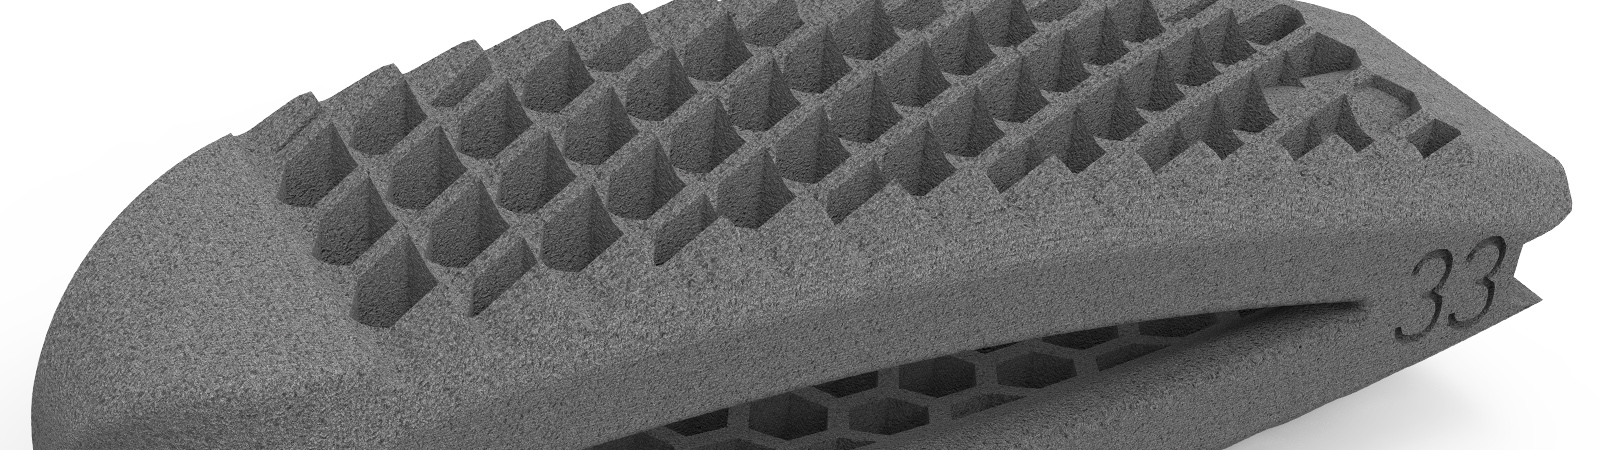

zurückMOONY-SLMTLIF aus Titan

MOONY bietet durch seinen schwenkbaren Universaleinbringer ein sicheres und einfaches Einbringen des Cages. Das patronenförmiges Design, sowie Finnen auf der Grund und Deckplatte des Implantates, lassen den Cage sehr elegant in den interkorporellen Bereich gleiten.